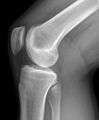

Fractures

Knee fractures are rare but do occur, especially as a result of motor vehicle accidents. There is usually immediate pain; swelling and one may not be able to stand on the leg. The muscles go into spasm and even the slightest movements are painful. X-rays can easily confirm the injury and surgery depends on the degree of displacement and type of fracture.

Knee X-ray

Knee X-ray (Front)